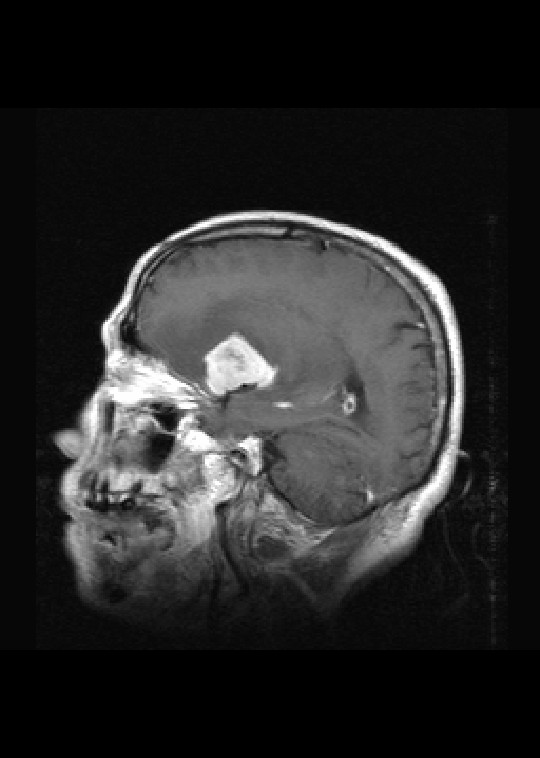

标题: MRI2527:脑部肿瘤,(病理结果:淋巴瘤)

(左额颞叶)非霍奇金淋巴瘤,b细胞性,弥漫性大b细胞型。免疫组化结果:cd45(lca) +,vimentin +,ck(ae1/ae3) -,ema -,cd3 -,cd20 +++,cd30 -,plap -,cd79a +,gfap -,alk -,s-100 -。

左侧基底节区病灶t1wi呈不均匀稍低信号,t2wi呈稍高信号,周围伴有水肿。增强扫描呈均匀团块样或者抱拳样明显强化,相邻的柔脑膜亦见线样强化。首先考虑淋巴瘤。可惜没有ct平扫,如果ct平扫病灶呈高密度,那么更支持pcnsl的诊断。

病理结果:(左额颞叶)非霍奇金淋巴瘤,b细胞性,弥漫性大b细胞型。免疫组化结果:cd45(lca) +,vimentin +,ck(ae1/ae3) -,ema -,cd3 -,cd20 +++,cd30 -,plap -,cd79a +,gfap -,alk -,s-100 -。

左侧基底节区病灶t1wi呈不均匀稍低信号,t2wi呈稍高信号,周围伴有水肿。增强扫描呈均匀团块样或者抱拳样明显强化,首先考虑淋巴瘤。